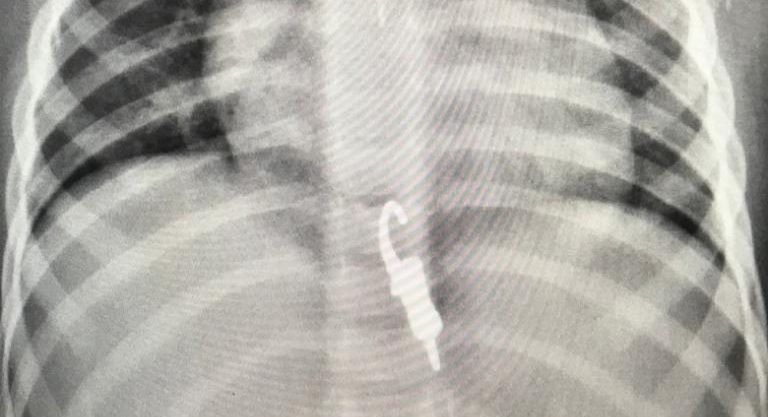

A mãe de uma menina de 2 anos, moradora de Botucatu, passou por momentos de desespero na última quinta-feira (14), após a criança engolir a parte metálica de um chaveiro.

De acordo com as informações, a criança brincava com a irmã mais velha no momento do acidente. A mãe rapidamente socorreu a criança e levou até o Pronto- Socorro onde a menina passou por exames de imagem.

No raio-x inicial, foi localizado o objeto dentro do esôfago da criança que precisou ficar internada para acompanhamento médico. Sem causar nenhuma perfuração de órgãos, o chaveiro desceu para o estomago e em seguida para o intestino, até que foi expelido com as fezes neste sábado (16).